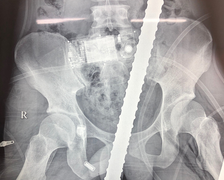

Ngày 21/1, Bệnh viện Hữu nghị Việt Đức tiếp nhận trường hợp nam bệnh nhân P.K.H., 16 tuổi, ở Hưng Yên bị sưng đau tinh hoàn bìu phải do chấn thương thể thao.